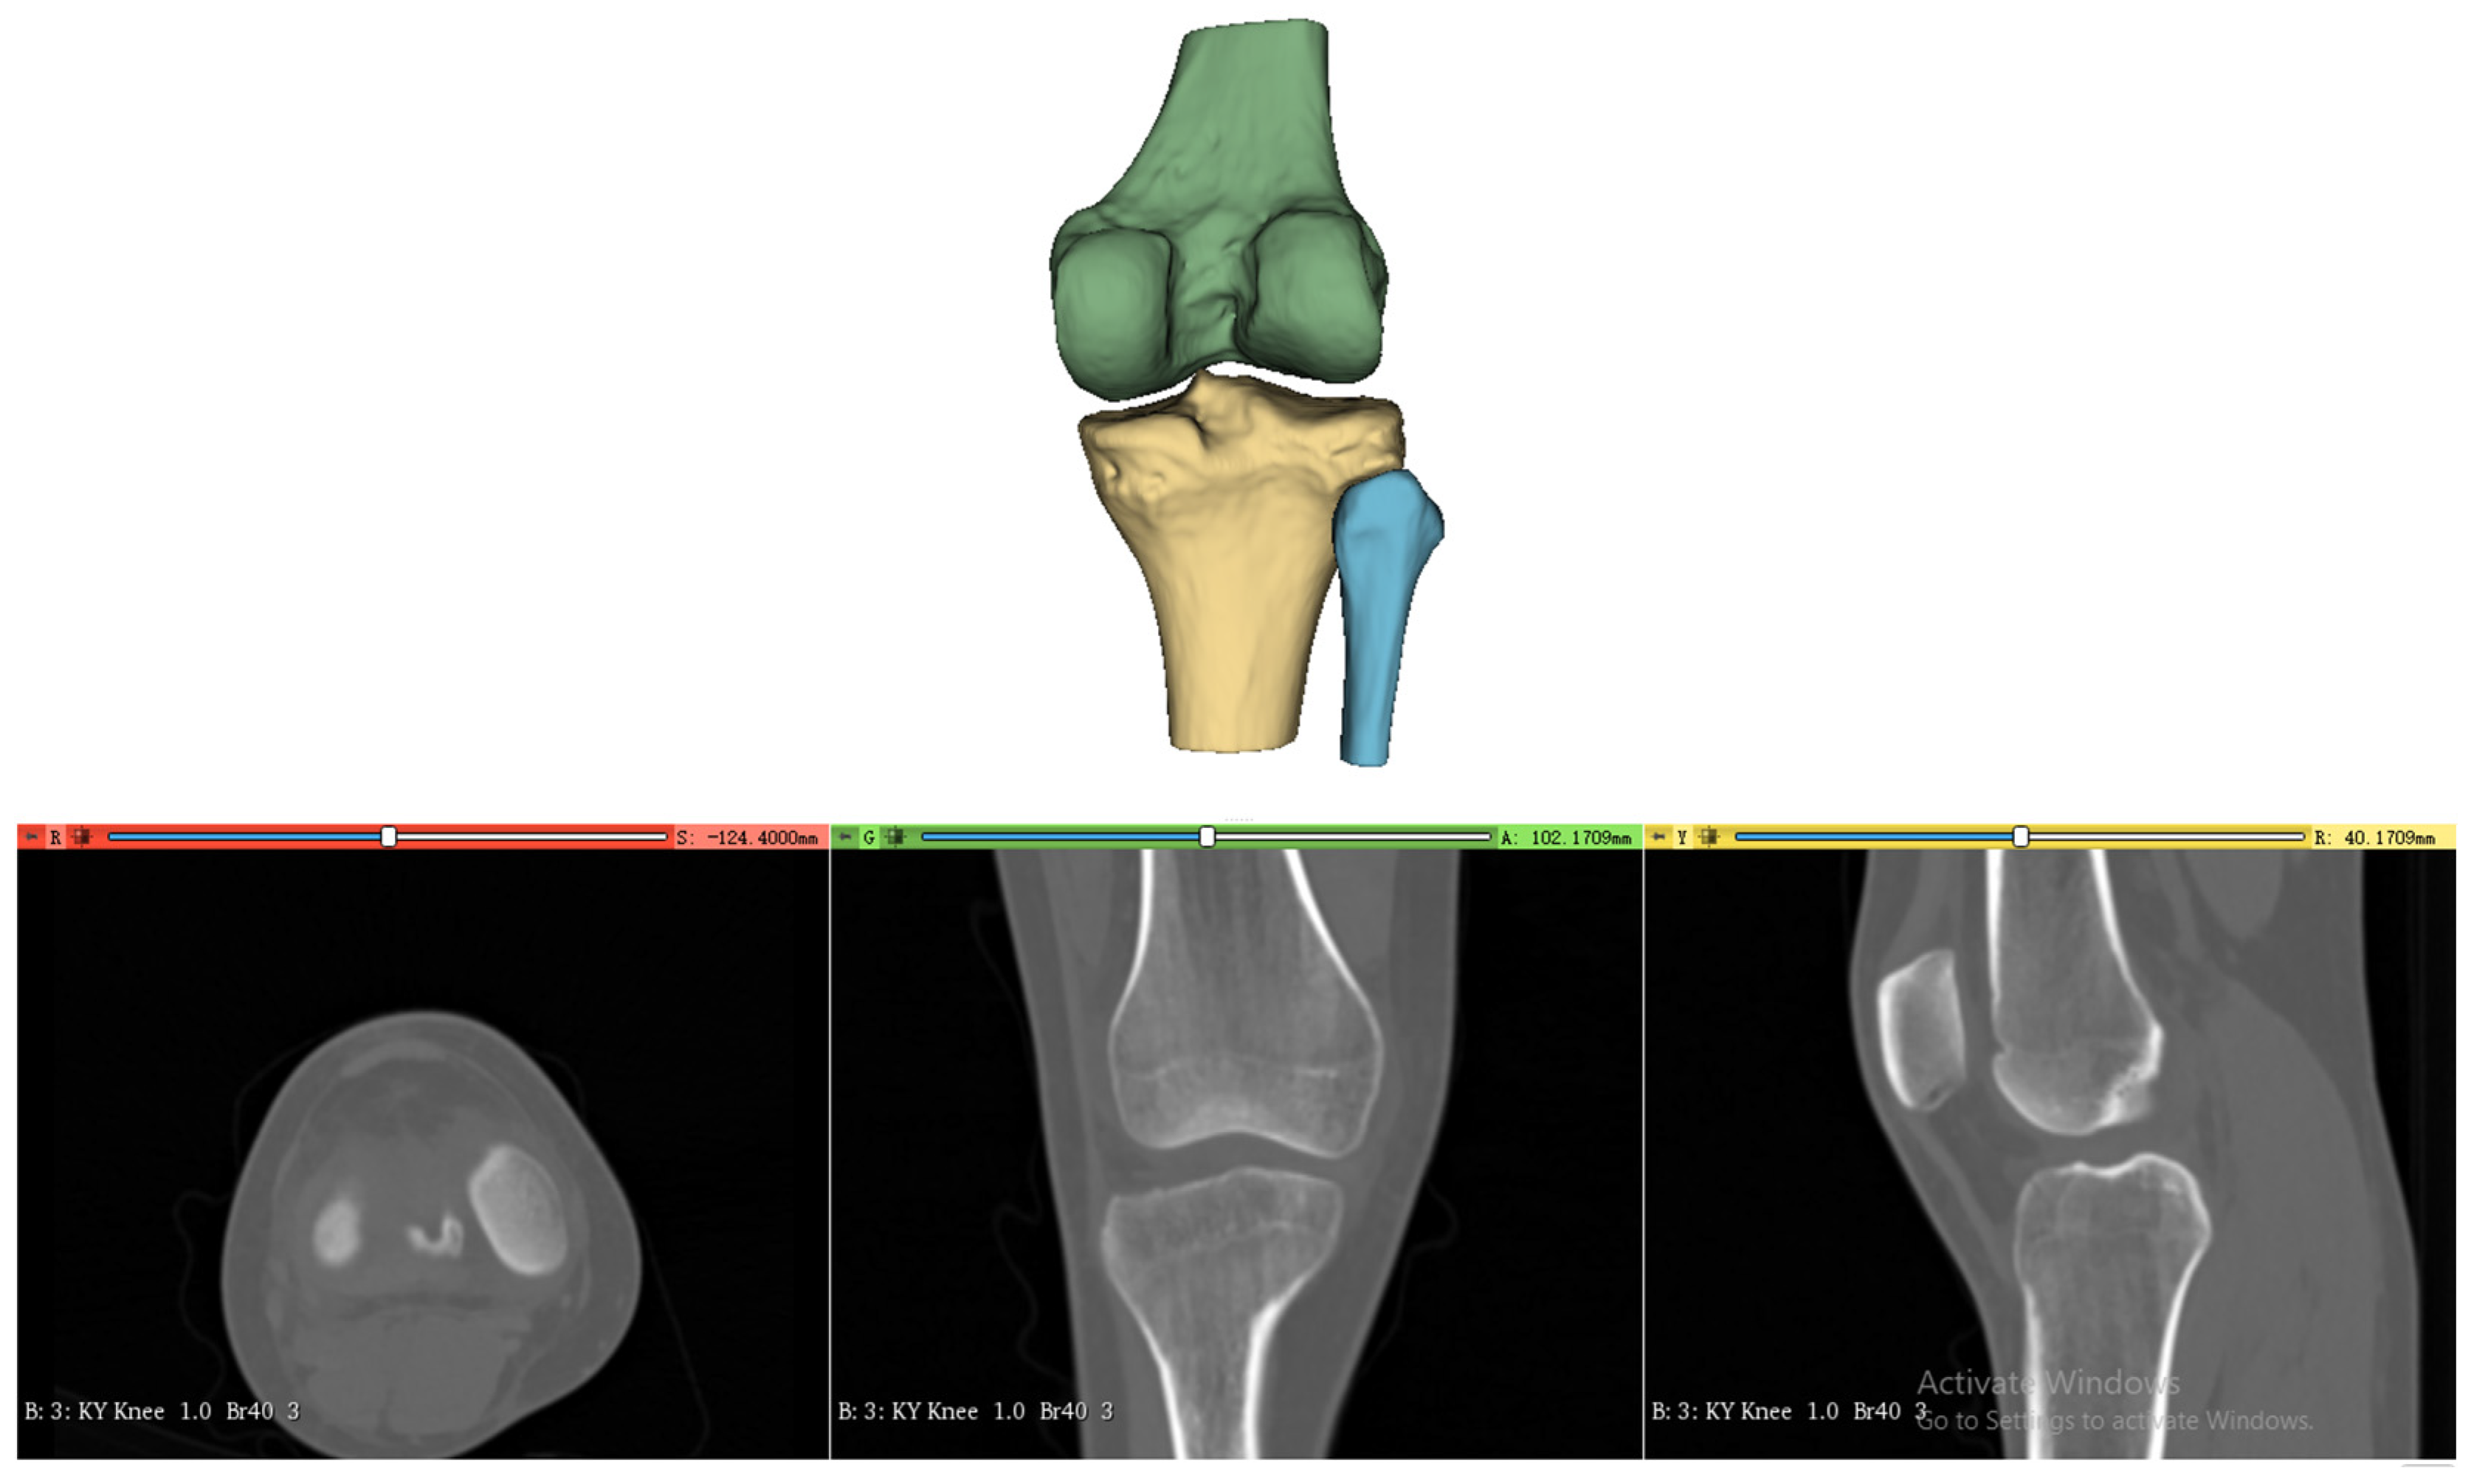

2.2. 3D Femoral Model Processing

2.3. Geometric Analysis and Optimization of Femoral Condylar Profiles

2.4. Extraction and Analysis of Lateral Condyle Feature Curves

2.4.1. Curvature-Based Feature Curve Extraction on Lateral Condyle Surface

2.4.2. Anatomical Region-Based Feature Curve Refinement

2.5. Establishment of B&H Grid on the 3D Lateral Condylar Model